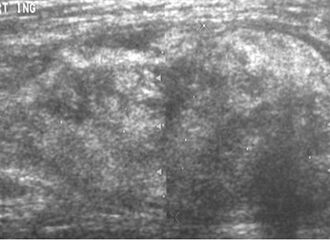

-

Ultrasonography of a liposarcoma mimicking a lipoma. A homogeneous hypoechoic mass presenting with the same appearance of lipoma. It was clinically distinguished as having rapid growth.[5]